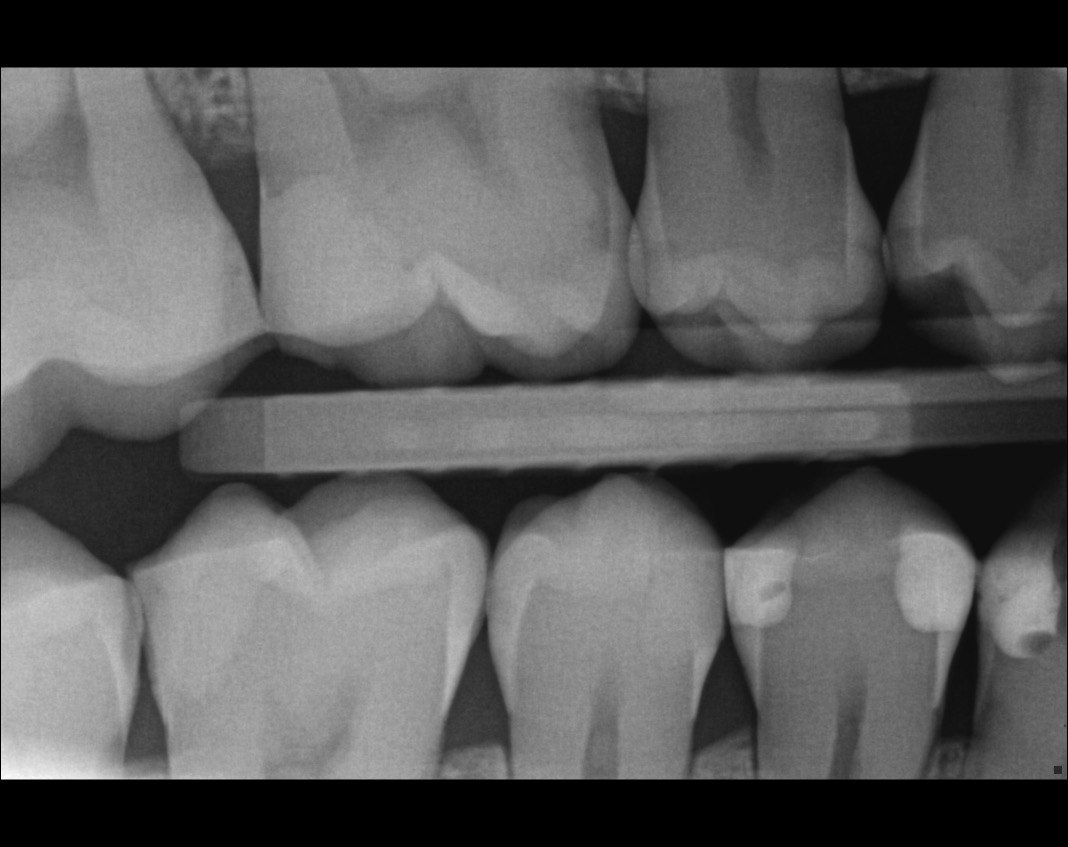

Question 1: What materials cannot be seen in the print of the X ray?

Question2: Which surface shows overhang?

Question 3: Which option is not evident on the print of the X ray?

Question 4: Which options cannot be seen in the print of the X ray?

Question 5: What options cannot be selected for tooth # 4.6?

Question 6: What options cannot be seen in the print of the X ray?

Question 7: What option cannot be identified on the print of the X ray?

Question 8: What condition can be seen in the X ray?

Question 9: Which option cannot be seen in the lower jaw?

Question 10: Which option can be selected for the following X ray?